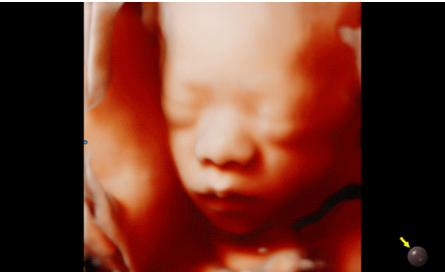

Hera i 10繼承并升級了全球首款5D超聲“三星麥迪遜WS80A”的“晶體結(jié)構(gòu)”成像理念,即將CrystalBeam?波束形成技術(shù)、CrystalLive?超聲成像引擎、S-Vue Transducer?視覺傳感器集于一身,提供更清晰的圖像。

3D/4D成像方面,Hera i 10通過結(jié)合先進(jìn)的圖像渲染技術(shù),著重加強(qiáng)了邊緣和小結(jié)構(gòu)的可視化能力。